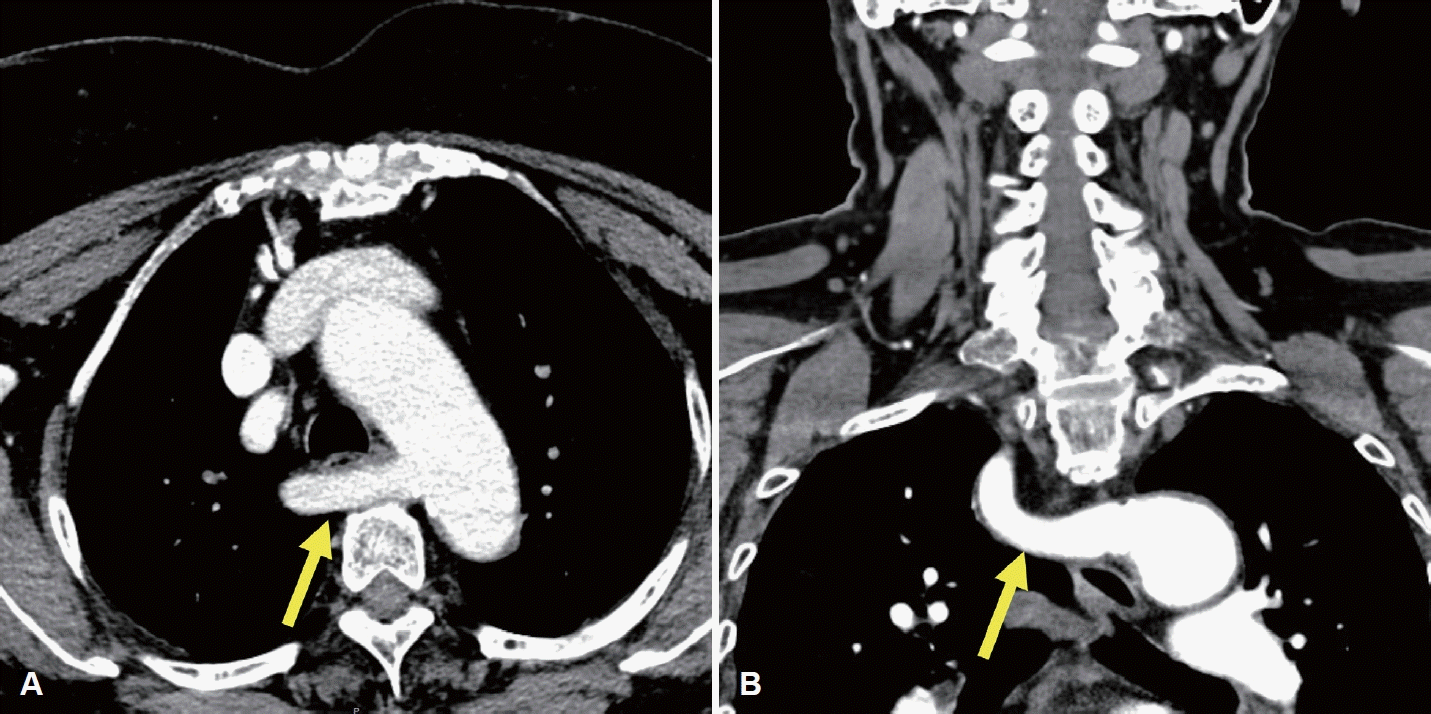

78세 여성이 한 달 전부터 발견된 전방 경부 종괴를 주소로 내원하였다. 신체검사 및 촉진 결과 갑상선 종괴가 의심되었고, 수일 후 시행한 초음파 검사에서 좌측 협부에 44 mm 크기의 갑상선 결절이 확인되어 중심바늘생검(core needle biopsy)을 시행하였으며, 갑상선 유두암(papillary thyroid cancer)이 진단되었고 초음파와 조영증강 갑상선 CT (thyroid CT)를 시행하였으며 수술 전 임상병기는 cT3bN0으로 판정되었다. 경부 초음파 검사는 고해상도 초음파 기기(EPIQ7, Philips Healthcare)와 5-12 MHz 선형탐촉자를 사용하여 갑상선 및 두경부 초음파에 숙련된 영상의학과 전문의에 의해서 수행되었다. 조영증강 갑상선 CT는 갑상선암 진단에 최적화된 대한갑상선영상의학회에서 제시한 표준검사기법으로 수행되었으며[1], 조영제 주입 후 35초 시점에 영상이 획득되었고, 2 mm 절편 두께로 횡단면, 관상면, 시상면 영상이 재구성되었다. 갑상선 전절제술 및 중앙 경부절제술을 계획하였고 thyroid CT에서 우측 이상 쇄골하동맥이 확인(Fig. 1)되어 비반회후두신경 가능성을 고려하여 비반회후두신경 평가를 위해 수술 전 경부 초음파를 추가로 시행하였다. 비반회후두신경의 초음파 평가는 설골 부위에서부터 미주신경을 초음파로 확인한 후에 미주신경을 하방으로 연속적으로 추적하여 미주신경에서 내측으로 분지되는 신경 유무를 평가하였다. 본 증례에서는 초음파 검사에서 갑상연골 높이의 미주신경으로부터 직접 분지되어 총경동맥 후방 쪽으로 주행하는 저에코의 신경 가지를 확인하였다(Fig. 2). 이후 예정된 수술을 시행하였으며, 피부 절개 후 갑상선 검체를 박리하는 과정에서, 한국 표준화된 신경모니터링 방법2)을 사용하여 수술 중 신경모니터링을 적용하였고, 모니터는 잘 작동하였다. 수술 시 type II 비반회후두신경을 확인하였으며(Fig. 3), 수술 중 신호손실(loss of signal) 등의 문제는 없었으며, 수술 직후 및 외래 추시 시 내시경 검사에서 성대마비는 관찰되지 않았으며(Fig. 4), 입원 중 특이 합병증이 관찰되지 않았다. 병리 결과는 유두암, 고전형(classical type), 단일 결절(3.9×3.0×3.0 cm), 갑상선 외 침범(macroscopic extrathyroidal extension) 및 좌측 6번 경부 구획에서 한 개 림프절에서 미세 림프절 전이가 확인되었다. 림프혈관 침윤, 신경 침윤, 외측 절제면 침범은 없었다. 환자는 내분비내과에서 정기적인 추적 검사를 진행하며, 방사선 요오드 치료(radioactive iodine)를 권고하였으나 환자의 의사에 따라 시행되지 않았다. 내분비내과에서는 권장했지만, 환자는 이를 거부하였다. 추적 검사에서는 T3, T4, 갑상선자극호르몬, 갑상선글로불린 등을 포함한 갑상선기능 검사 및 화학검사에서 정상 범위 수치를 보였다.

Preoperative enhanced thyroid CT images of an ARSA. A: Axial enhanced CT shows the ARSA (arrow) arising from the aortic arch and coursing posterior to the esophagus. B: Coronal enhanced CT shows the retroesophageal ARSA (arrow). ARSA, aberrant right subclavian artery.